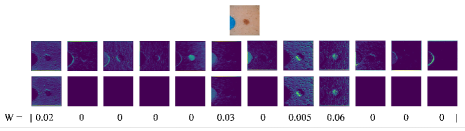

In this section, we visualize the outputs of both the channel selection and attention layers. As shown in Fig. 5, after applying the selection step, some of the less discriminative channels are completely turned off by the proposed channel selection.

After the selected channels are transferred to the attention layer, the model learns to attend to the most important part(s) of the image, which helps in segmenting the target object(s) more accurately. A few samples of the attention maps for two of the proposed skip connections, used within the 2D U-Net (Fig. 6) and 3D V-Net (Fig. 7) architectures, are shown in Figs. 6 and 7 for the 2D skin lesion and 3D prostate MRI datasets. As can be seen in both Figs. 6 and 7, a model with only attention layer (i.e., only AT) tends to attend to several areas of the image; including both where the object is present and absent (note the red colour visible over the whole image). However, applying channel selection (i.e., ST) before the attention layer curtails the model from attending to less discriminative regions.

We also quantitatively analyzed the proposed learnable skip connections in terms of percentage of channels “turned off” (i.e., channels i for which is zero in the channel selection layer). For U-Net, and and for V-Net, and percentage of channels were off for MRI and skin datasets, respectively. Since transferring only one channel (instead of N channels) as the output of the SAT gate, reduces the needed number of convolution kernel parameters in the other side of skip connections, we further report the total number of parameters before and after applying the proposed method (i.e., SAT) in Table 3. As can be seen, the total number of parameters are reduced by 30.2% and 7.3% and 30.6% and 8.02%, for U-Net and V-Net, respectively for MRI and Skin datasets. For The One Hundred Layers Tiramisu network the number of parameters are reduced by for all the datasets. Further note that the proposed method reduces the number of convolution operations after each concatenation to almost 50% as demonstrated next. As an example, after an original skip connection that carries 256 channels and concatenates them with another 256 channels on the other side of the network, the consequent convolution layer right after the concatenation will need 512 (=256+256) convolution operations. However, as the proposed skip connections carry only one channel, for the same example, only 257 (=1+256) convolutions are needed. Note that the reason for the difference in the number of parameters in the original networks in Table 3 is that because of memory limitation we reduced the number of layers and/or channels for different datasets.